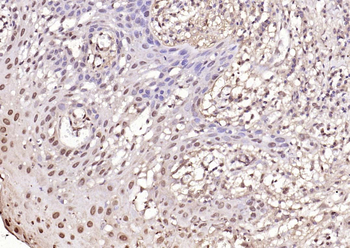

100 μl, 50 μl, 200 μl - ATF4 Recombinant Rabbit Monoclonal Antibody [orb704304]Featured

FC, ICC, IF, IHC-Fr, IHC-P, WB

Human

Mouse

Rabbit

Recombinant

Unconjugated

50 μl, 100 μl - MARK3 Recombinant Rabbit Monoclonal Antibody [orb704310]Featured